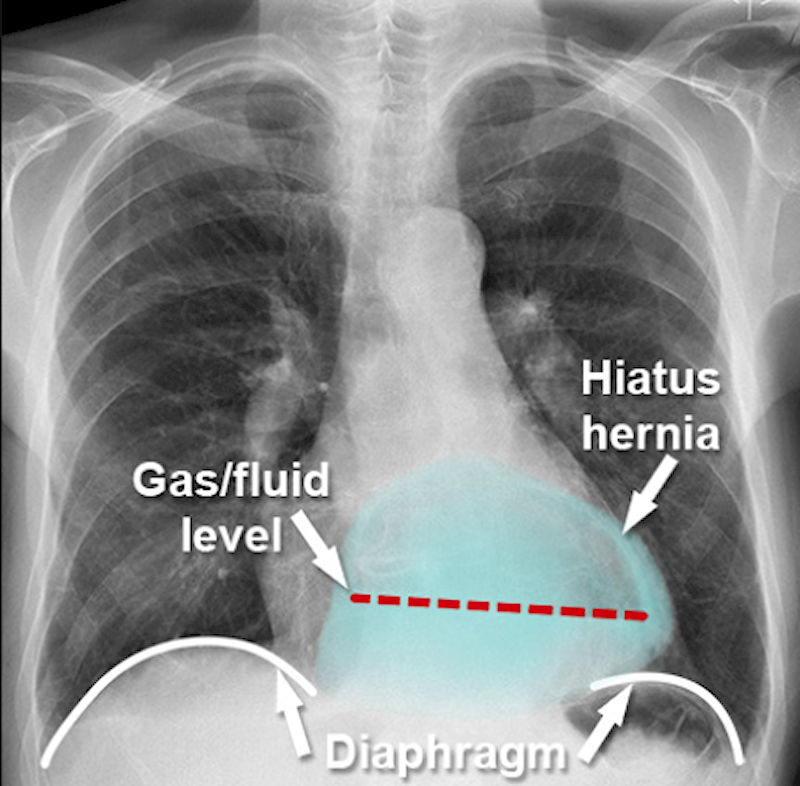

Грыжа пищеводного отверстия диафрагмы (ГПОД) возникает, когда верхняя часть желудка выпячивается через отверстие диафрагмы в грудную клетку. Диафрагма — это мышечный барьер, отделяющий брюшную полость от грудной. Грыжа возникает, когда какой-либо орган или ткань выпячивается через слабое место в тканевом барьере, который обычно его удерживает. Грыжи встречаются часто и грыжи пищеводного отверстия диафрагмы относятся к наиболее распространённым типам.

рис.1 Грыжа пищеводного отверстия диафрагмы

Рентген с контрастом (барием) — рентген грудной клетки использует для получения чёрно-белых изображений внутренней части грудной полости, где расположен пищевод чтобы определить размер и тип ГПОД.